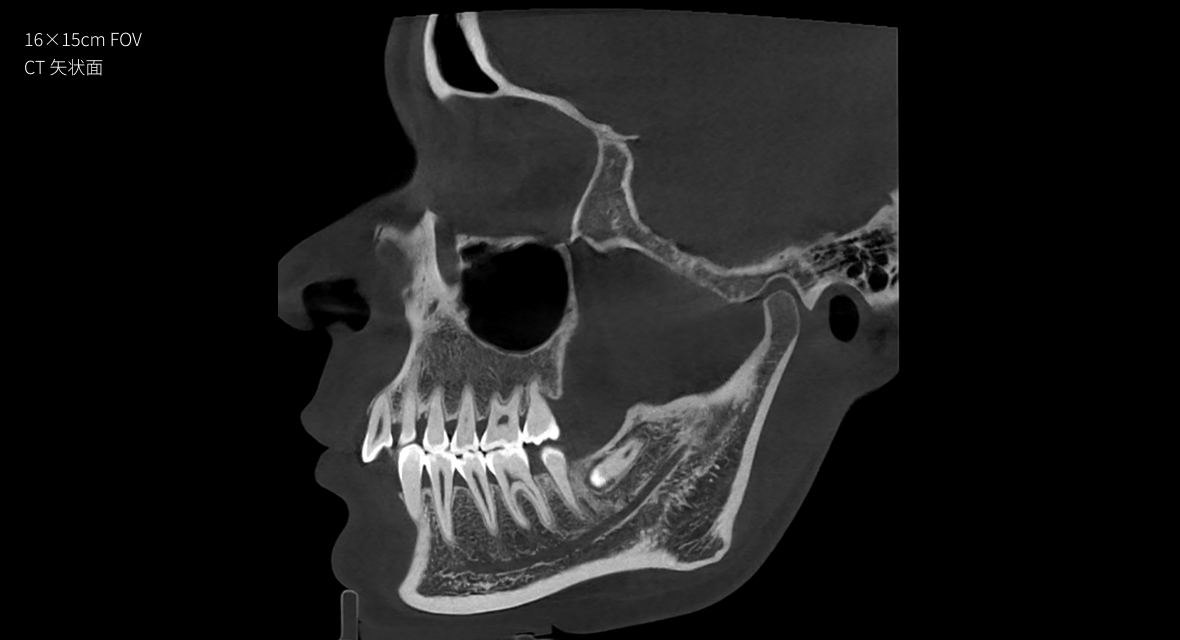

16×15cm

非拼接大视野

28lp/cm

高精准